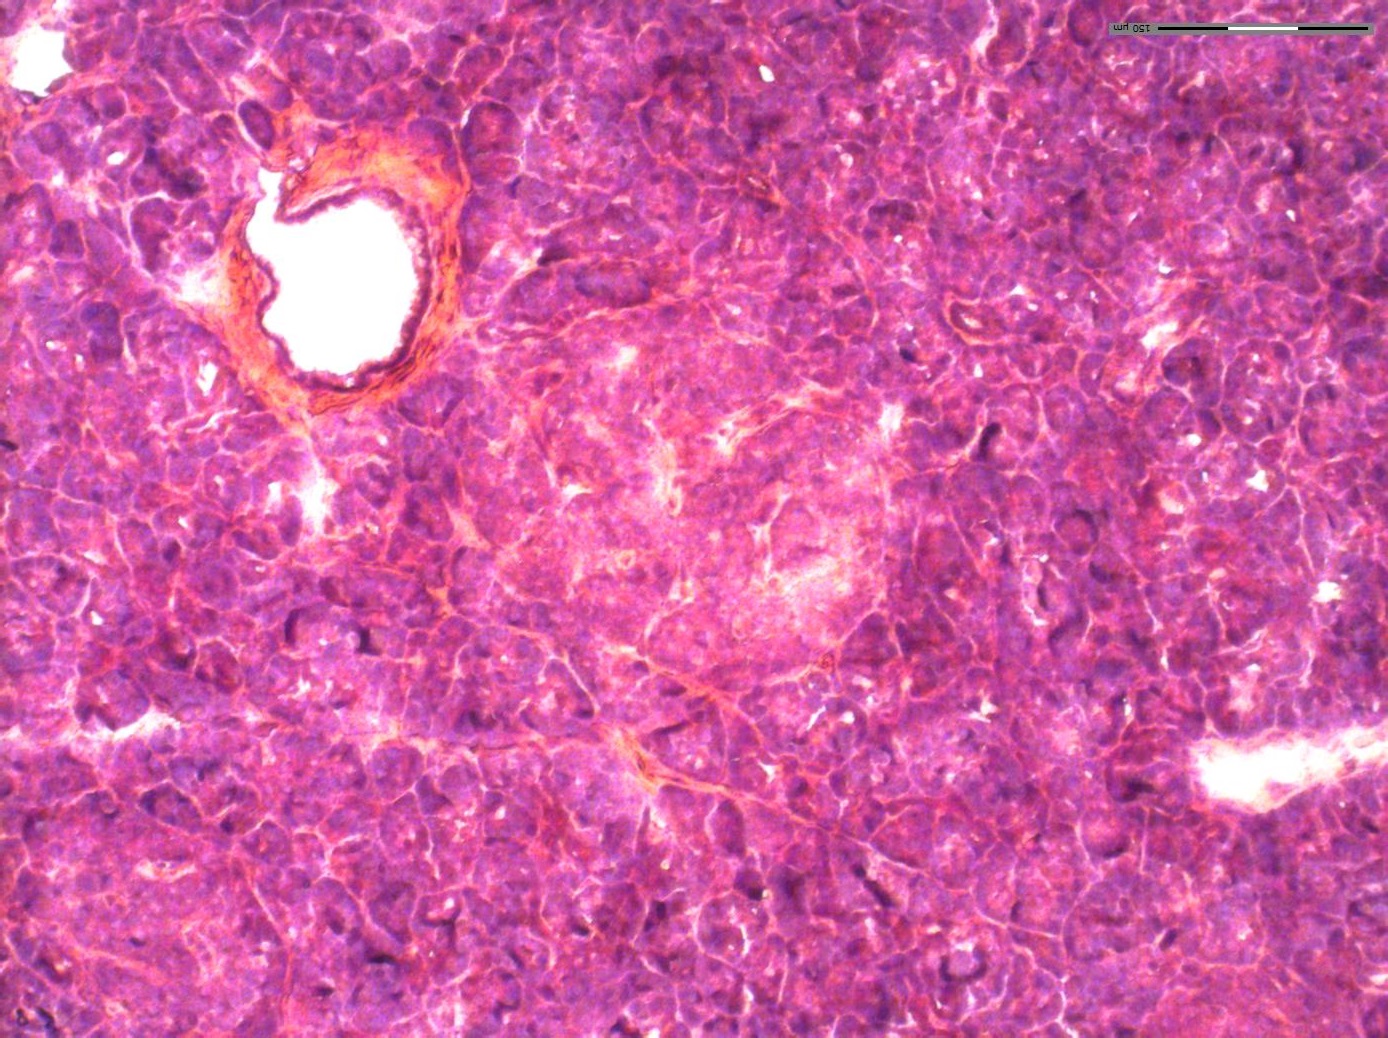

Human pancreatic tissue sections were imaged with multiplex immunofluorescence using DAPI (nuclear), INS (insulin/beta cells), and GCG (glucagon/alpha cells) channels at 10X magnification.

Each cell was classified as alpha, beta, or acinar based on RGB intensity thresholds from the three immunofluorescence channels.